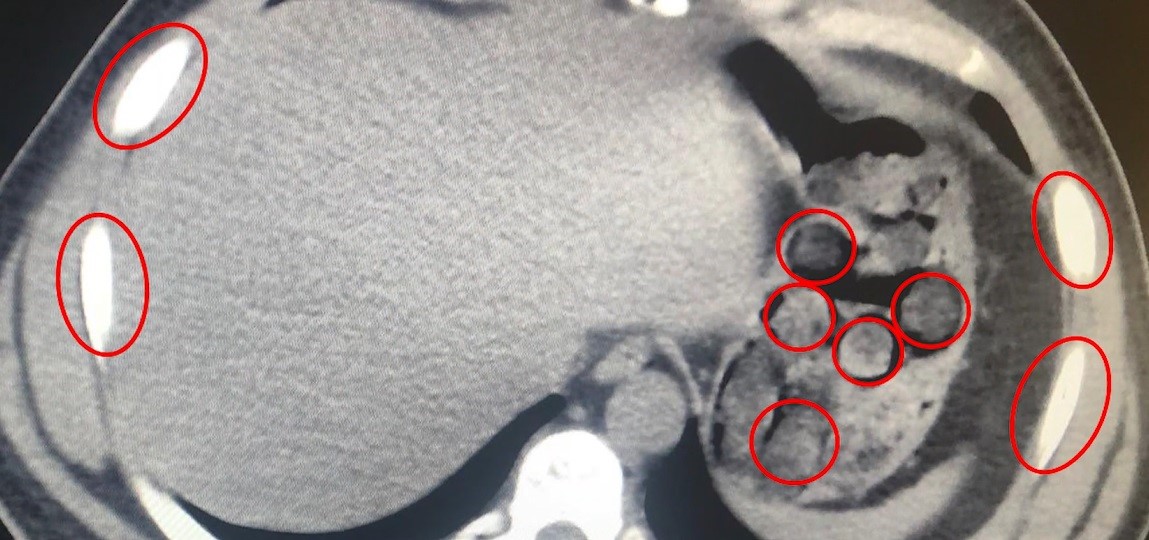

Bitlis İl Emniyet Müdürlüğü Narkotik Suçlarla Mücadele Şube Müdürlüğü ekipleri, uyuşturucu ile mücadele kapsamında önemli bir operasyona imza attı. Tatvan ilçesinde durdurulan bir otobüste yolcu olarak seyahat eden yabancı uyruklu 2 kişi gözaltına alındı. Şahısların yapılan tıbbi müdahalesinde, yuttukları 136 kapsül halinde toplam 1 kilo 48 gram metamfetamin ele geçirildi.